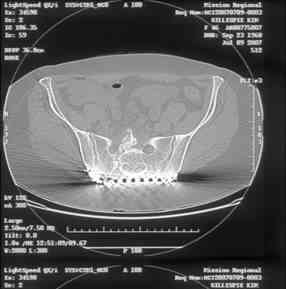

Here is a magnified view. Sorry about the quality but the CT was scanned into our system.

dave

Thank you...it might help to remove the disengaged and other iliosacral screws then insert longer lag screws into the upper sacral segment and if anatomically feasible into the second sacral segment as well.

You could do it percutaneously and even add an electrical stimulation device if that seems reasonable.

At this point, I'd ignore the right pubic root issue if asymptomatic.

If simple measures such as those above fail, then you could remove it all, take down the sacral fracture site, refix with alternate techniques, and bone graft.